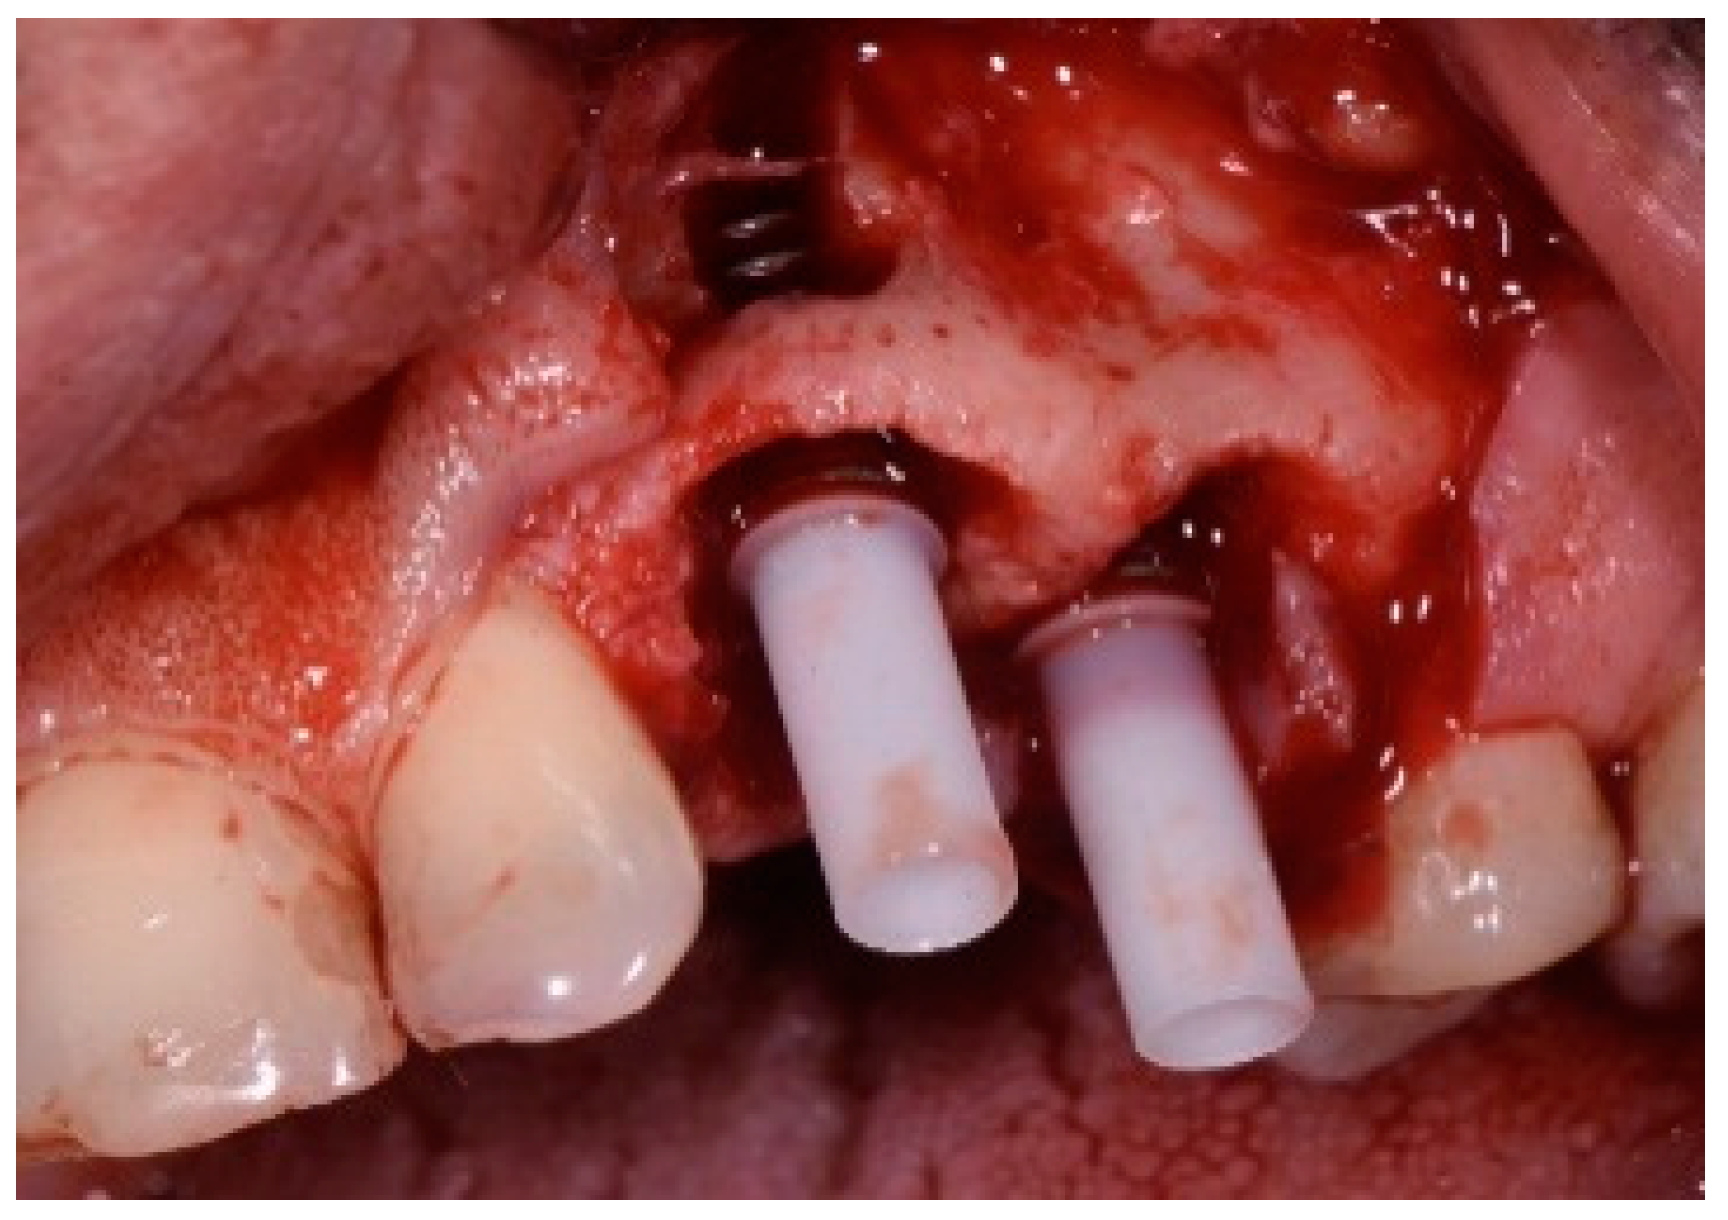

The patient accepted the proposed treatment plan. The preoperative surgical protocol described in patient 1 was followed. An L-shaped aesthetic flap design was chosen to treat this case. The flap started with an incision extending from the distal line angle of the central incisor to the mesial line angle of the canine. A vertical incision was carried out past the mucogingival junction, followed by the elevation of a full-thickness flap. The remaining tooth root was extracted, maintaining the existing facial bone (Figure 9).

Figure 9.

Clinical view of implant replacing.

The surgical protocol was followed as described for the previous patient. Likewise, an implant was placed, followed by the placement of bone graft material over the defect and covered with a resorbable membrane. Six months later, the implant was fully intergraded (Figure 10), and the soft tissue appeared to be within normal limits (Figure 11). The implant was restored with a ceramic zirconia crown. Figure 12 presents the patient three years after treatment.

Figure 10.

Radiograph of the lateral incisor.